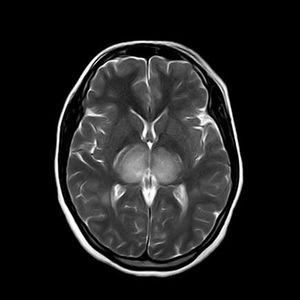

Case History: 27-year-old patient presented with history of seizures.